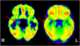

Focal epilepsy

Focal seizures (also called partial seizures and localized seizures) are seizures which affect initially only one hemisphere of the brain. The brain is divided into two hemispheres, each consisting of four lobes – the frontal, temporal, parietal and occipital lobes. [Source: Wikipedia ]